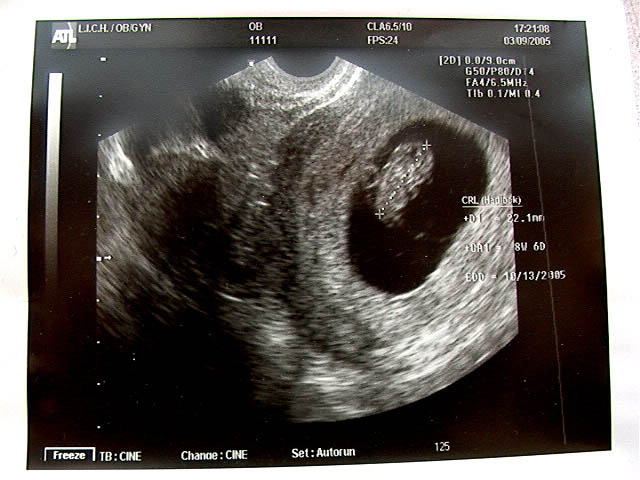

Sonogram 3/9/05